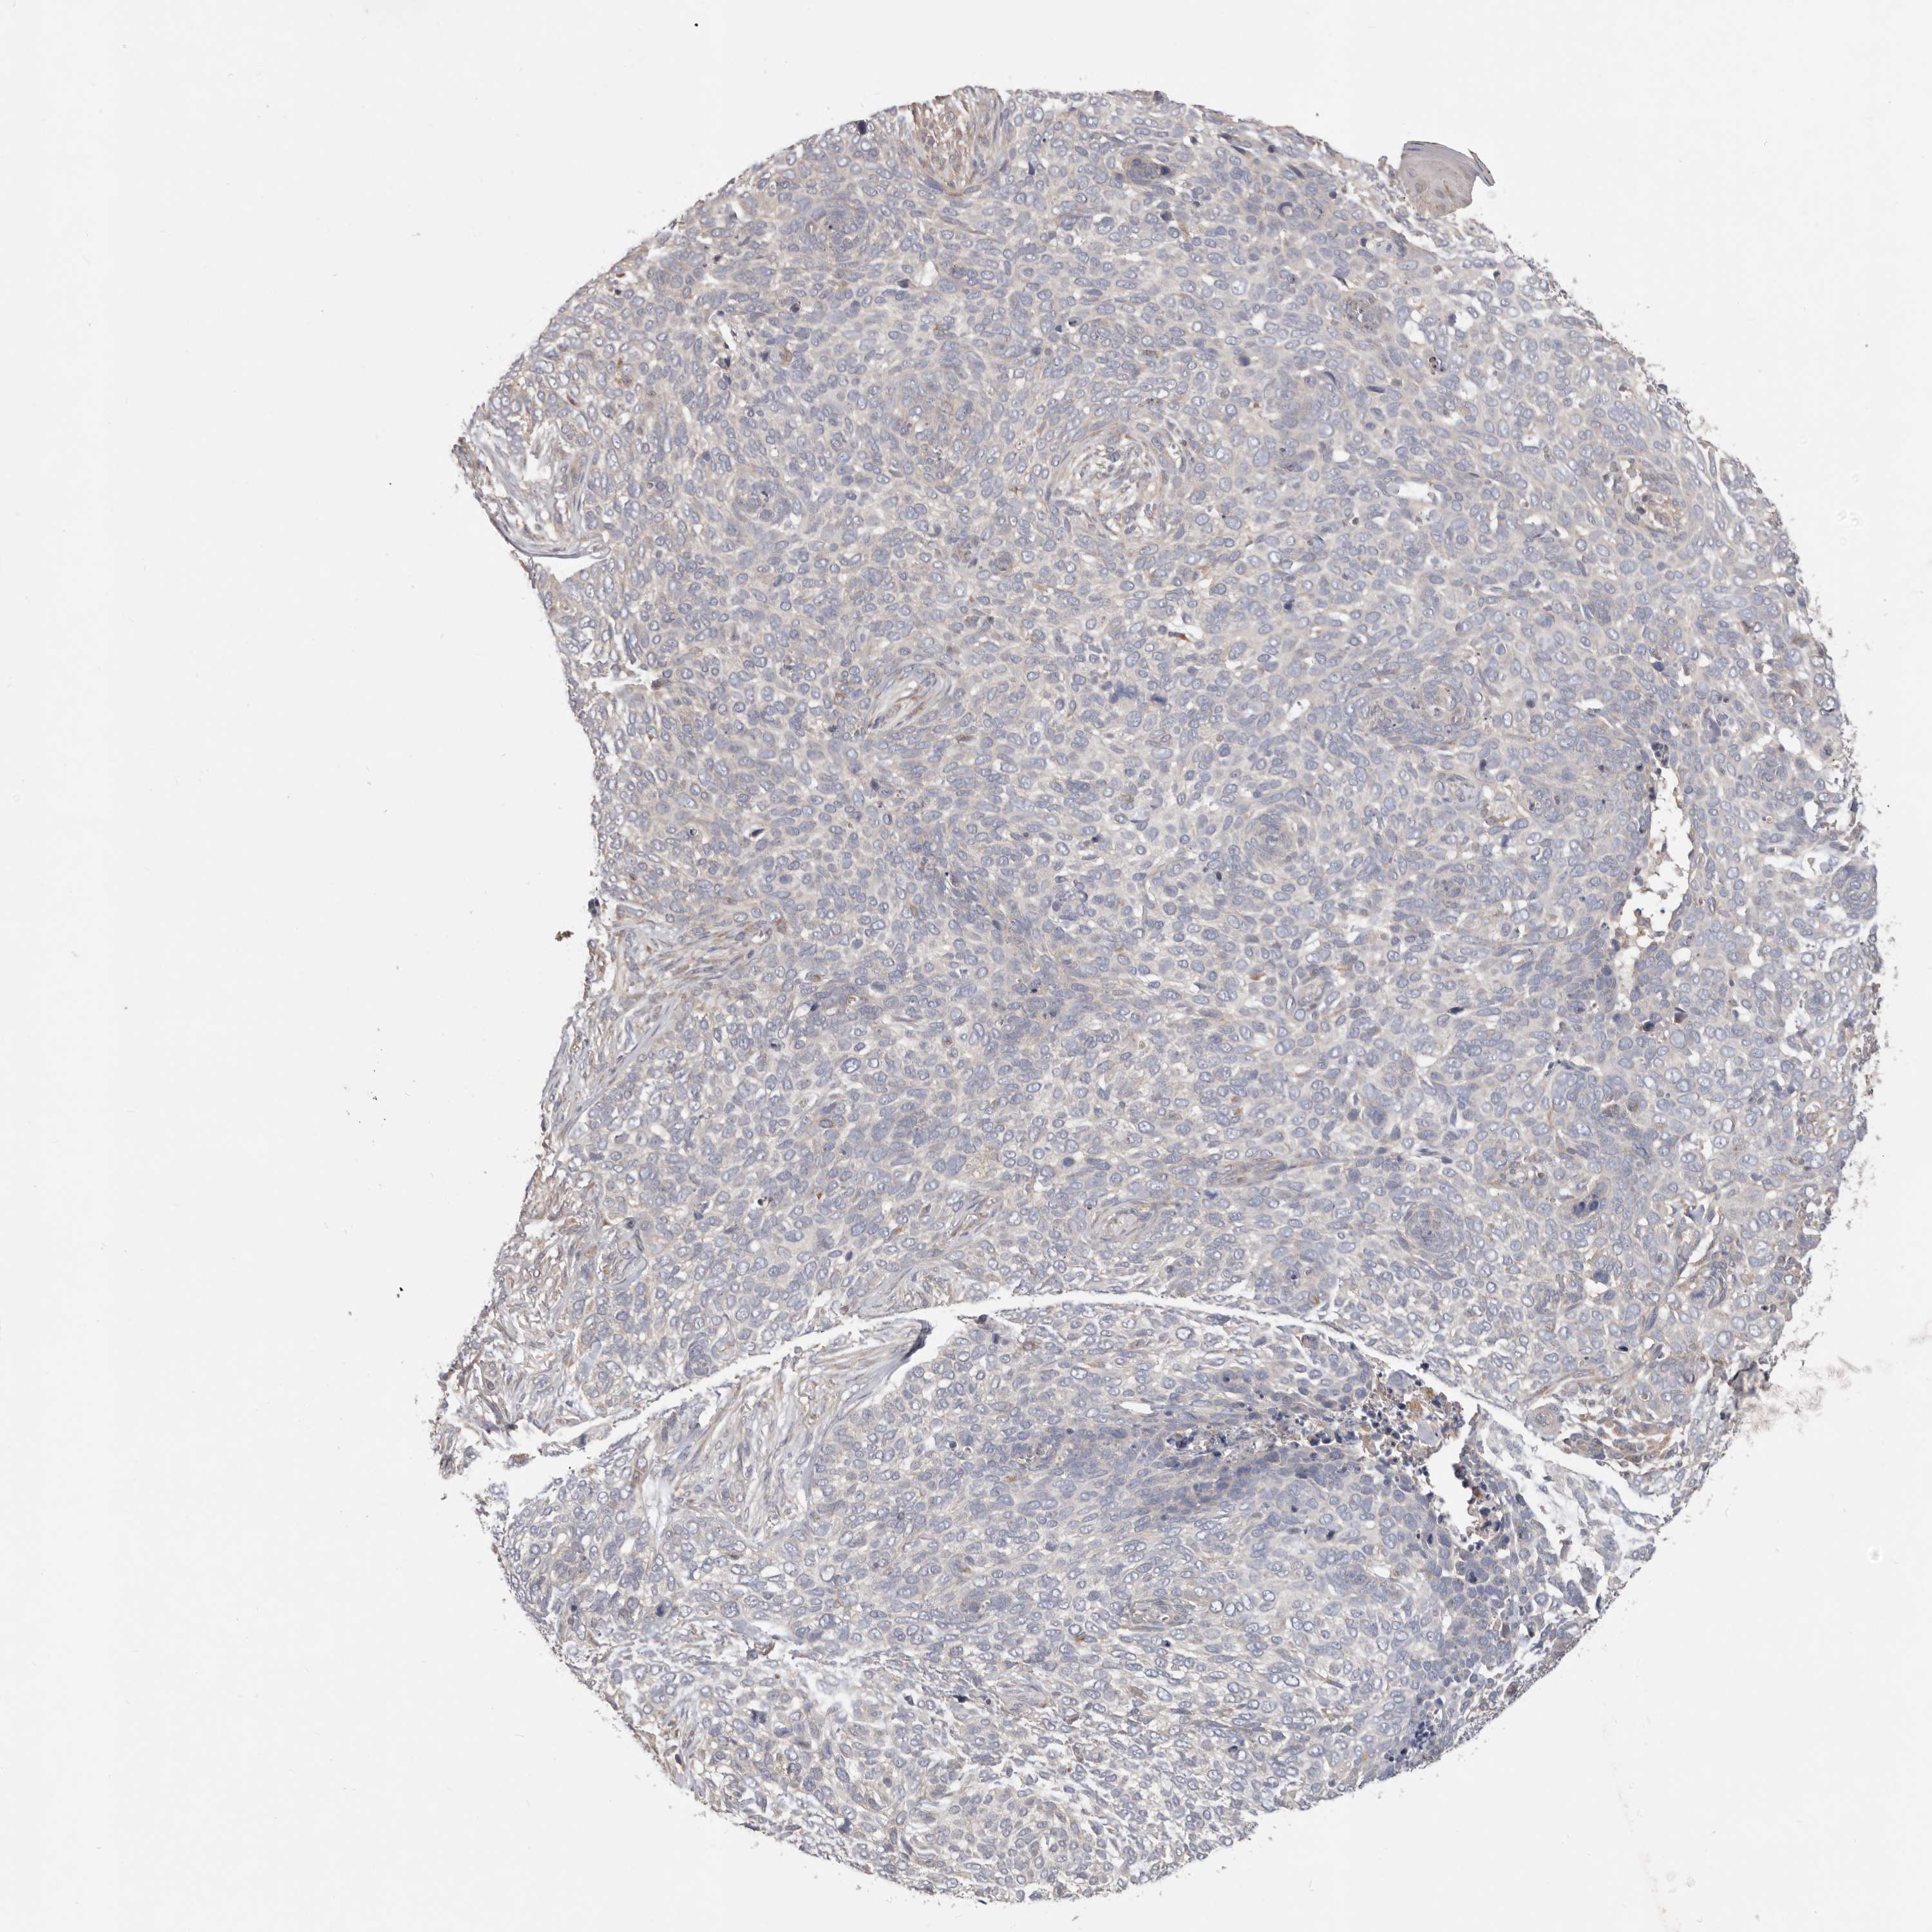

Basal cell and squamous cell cancer

SKIN CANCER - Protein expressioni

A mouse-over function shows sample information and annotation data. Click on an image to view it in a full screen mode. Samples can be filtered based on level of antibody staining by selecting one or several of the following categories: high, medium, low and not detected. The assay and annotation is described here.

Antibody stainingi

Antibody staining in the annotated cell types in the current human tissue is reported as not detected, low, medium, or high, based on conventional immunohistochemistry profiling in selected tissues. This score is based on the combination of the staining intensity and fraction of stained cells.

Each image is clickable and will lead to virtual microscopy that enables deeper exploration of all samples and also displays staining intensity scores, fraction scores and subcellular localization as well as patient and tissue information for each sample.

Basal cell carcinoma